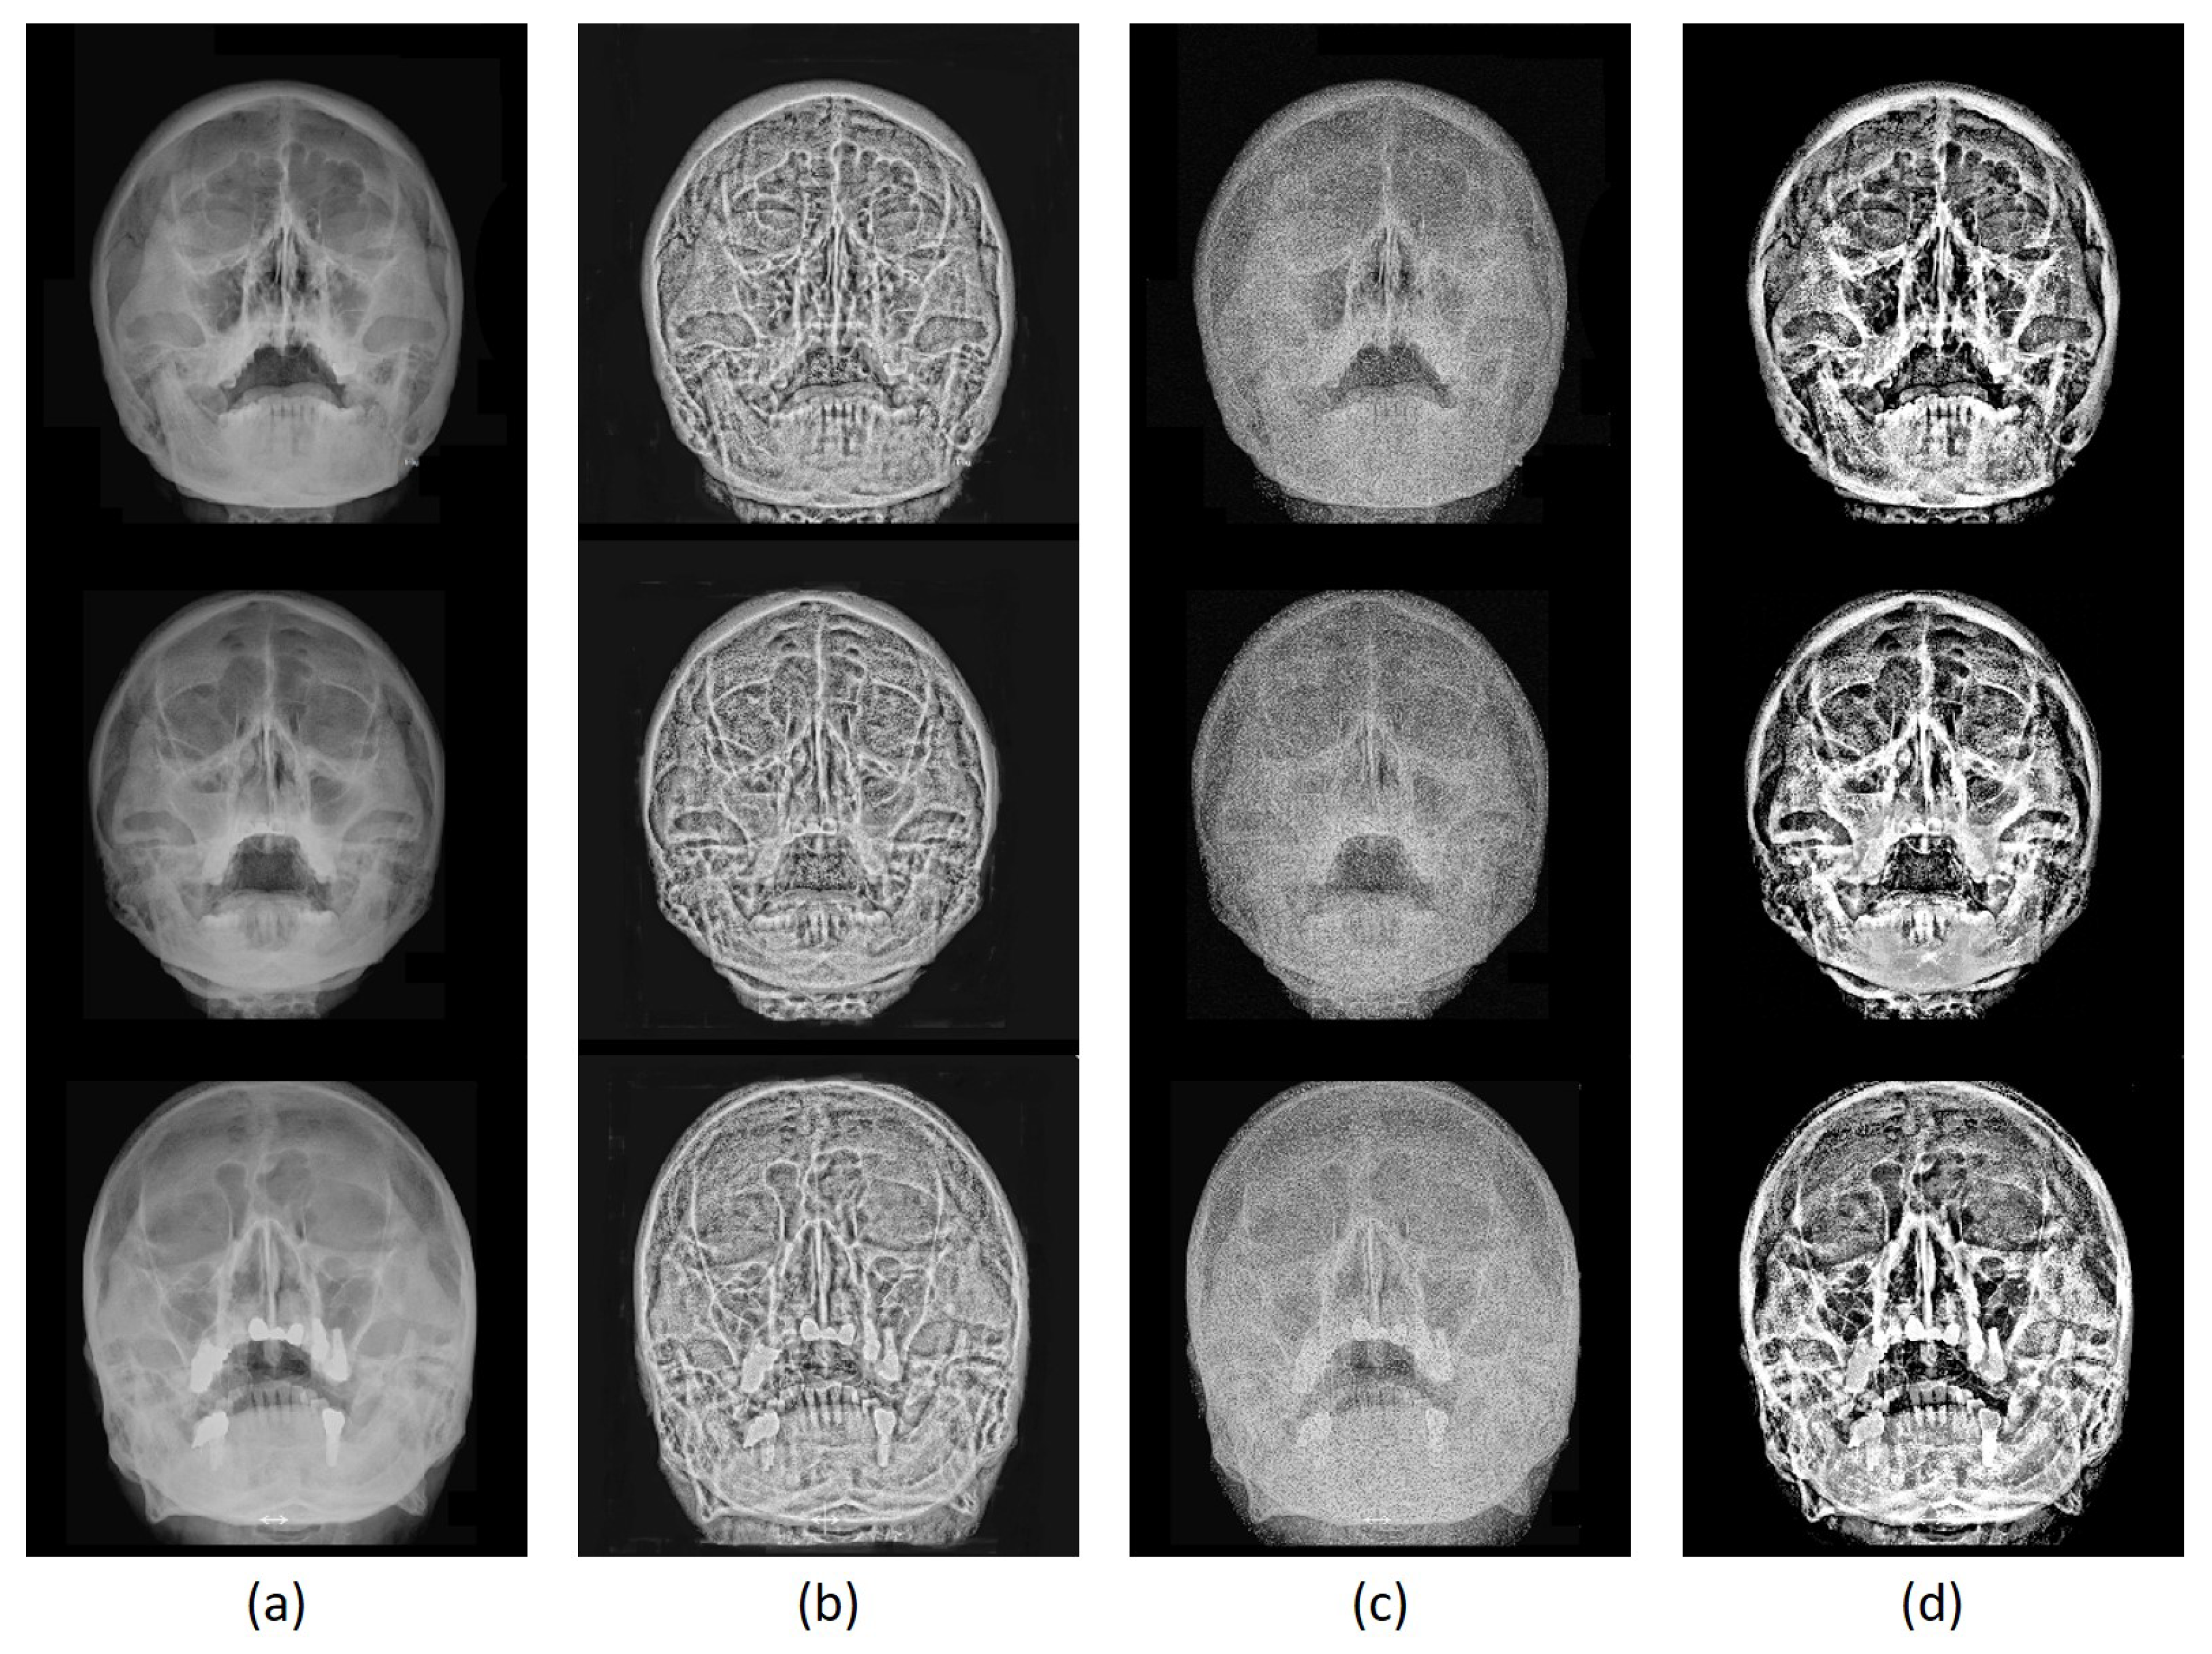

Figure 3 illustrates a montage of SXR resultants from the implemented techniques. The enhanced SZRS from HM-CLAHE in Figure 3b suggested a noticeable improvement, where the bone to soft-tissues are displayed clearly. Yet, there is much information on the enhanced SXR that were not enhanced properly, making it ambiguous to perform diagnosis. On the other hand, the LCE-BSESCS technique was able to keep details with distinct boundaries between bones and other soft-tissues; yet the contrast was not improved (Figure 3c). This condition may be the reason for the low scores in LCE-BSESCS in Table 3.

Figure 3.

Experimental result montages of various enhancement schemes. (a) Original SXR images from the negative N, the positive P, and the unknown folds () of the dataset (top–bottom). (b) Enhanced images from the HM-CLAHE [7]. (c) Enhanced images from the LCE-BSECSC [8]. (d) Enhanced images from the proposed ToMA method.

Contrary to the previous methods, ToMA achieved substantial enhancement on SXRs particularly on boundaries of bone and soft-tissues as shown in Figure 3d. The air spaces on the dark features are conditioned to be highly dark while the pixel values of mucous fluids are made higher. This condition helps the diagnosis to be more straightforward yet accurate, such as in Figure 3d. Ambiguous textures within the region of interest as shown in Figure 3d are also reduced by increasing the dark features (i.e., the air-filled regions). Compared to the prior arts, the proposed ToMA is able to modify the distinctive features between the air- to fluid-containing regions of the maxillary sinuses.